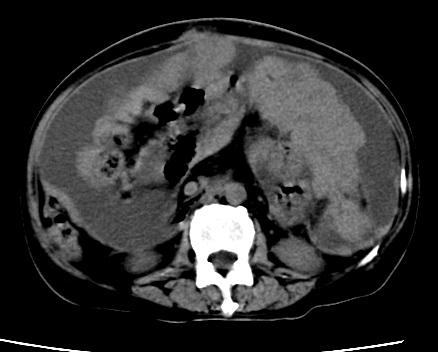

标题: CT23975:女61岁,腹部不适,明显消瘦 [打印本页]

标题: CT23975:女61岁,腹部不适,明显消瘦

既往5年前卵巢癌行子宫及附件切除,右乳癌术后一年,考虑腹膜转移?

大量腹水,考虑腹膜转移。肝脏低密度灶。1囊肿,2转移。

1)结合病史,考虑腹膜及网膜转移瘤。2)肝脏多发性低密度灶,不排除转移瘤。3)大量腹水。

考虑卵巢癌行子宫术后复发,并肝、腹腔 、大网膜转移可能性大。

大量腹水。